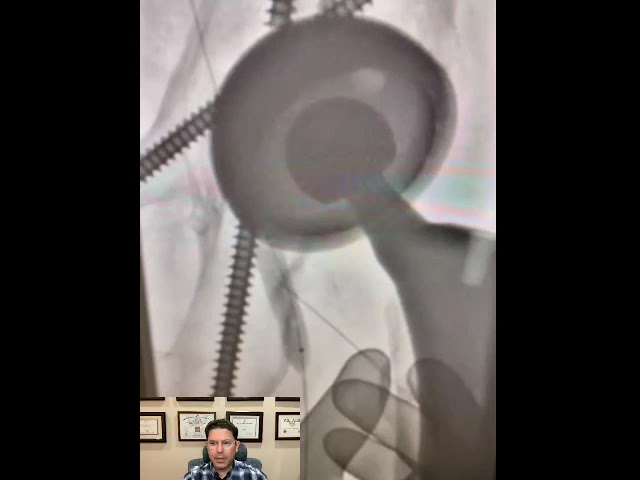

Dr. Hady Lichaa describes the management of a migrated iliac artery stent, with snaring into an adequate position.

Dr. Hady Lichaa exhibits a case of percutaneous aspiration of a large tricuspid valve vegetation.